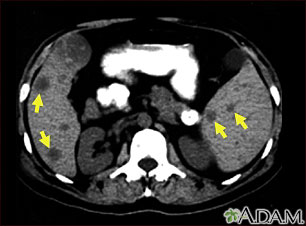

Tomografía computarizada de metástasis del bazo

Esta TC del abdomen superior muestra múltiples tumores en el hígado y el bazo que provienen (son metástasis) de un cáncer (carcinoma) intestinal original.